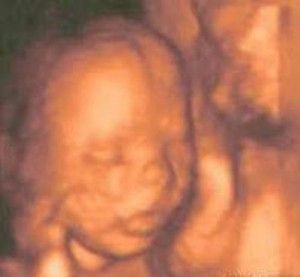

Vigésima semana de embarazo

En la semana veinte del embarazo ya se ha llegado a la mitad de la gestación.

El bebé llegará a medir unos 25 centímetros de longitud y s pesar unos 250 gramos. Después de esta semana sólo se percibe como la tripa irá creciendo más y más. Como ya tiene sus sentidos completamente desarrollados, el bebé puede oír cualquier sonido a partir de ahora, a pesar de que el líquido amniótico que lo rodea distorsiona lo que escucha, dándole una percepción similar a cuando oímos estando debajo del agua, pero aun así puede escuchar las voces, escuchar música (ponerle música tiene muchos beneficios), escuchará la respiración de la madre y la suya propia, los latidos de ambos y la sangre que fluye por los órganos que le rodean. También empieza a tener memoria por lo que todo lo que oye es bastante probable que luego lo reconozca.

Por otro lado comenzará a percibir la luz y además ya orina independientemente. Los movimientos son importantes para que el bebé empiece a tener movilidad y se notan las primeras patadas.